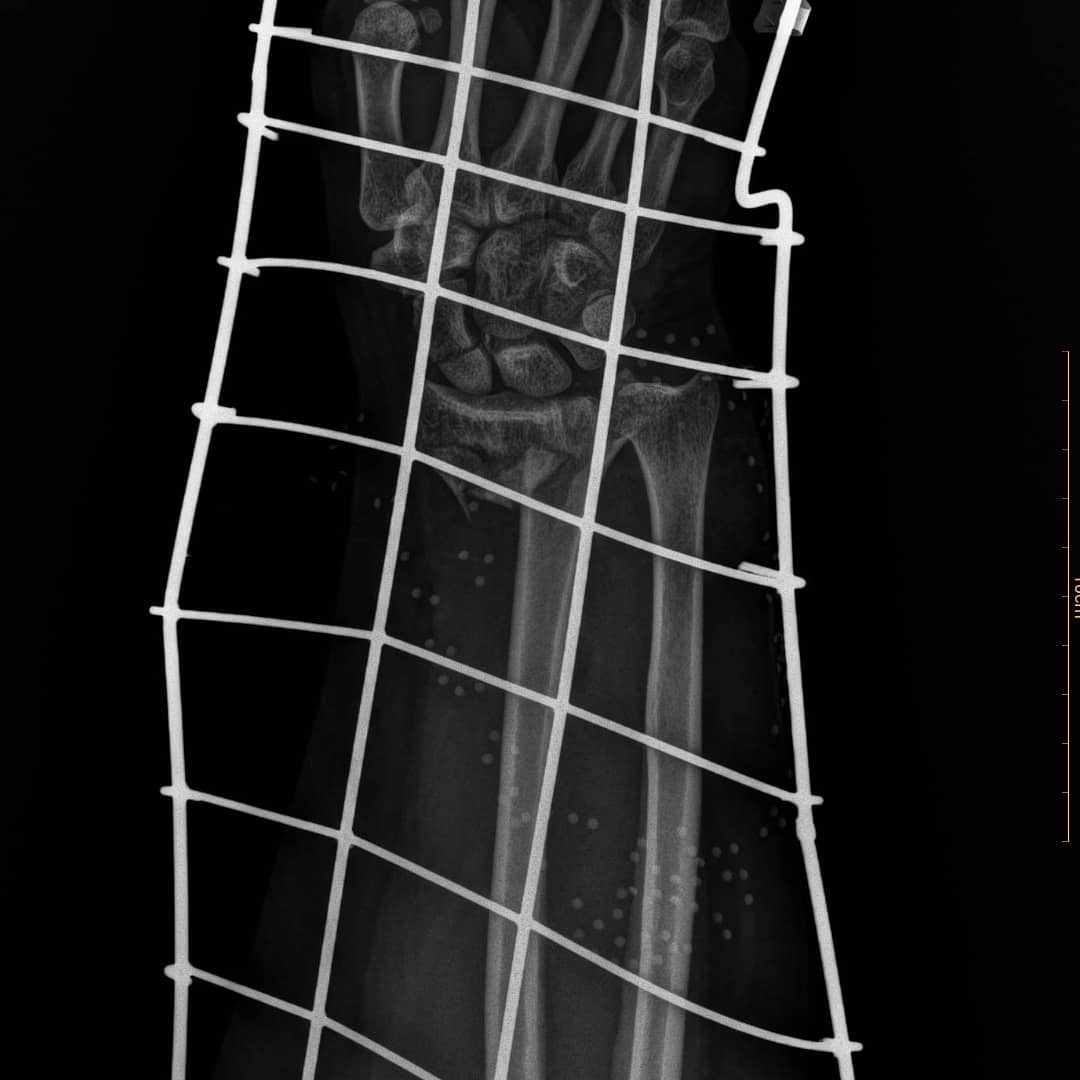

شکستگی خرد شده دیستال رادیوس و اسکافویید

خانم ۴۹ ساله که به دلیل واژگونی موتور چهارچرخ در ساحل انزلی، دچار شکستگی خرد شده مچ دست شده است. شکستگی دیستال رادیوس و اسکافویید و دررفتگی مفصل رادیواولنار به ترتیب فیکس شدند.